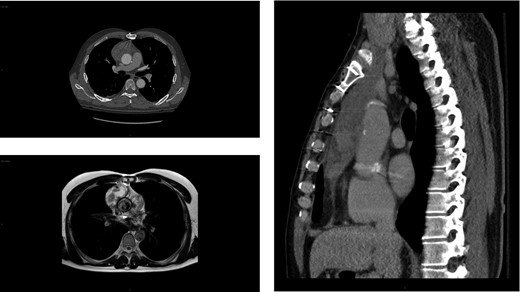

Workup at the outside hospital included computed tomography (CT) of the chest with administration of contrast material. This revealed a heterogeneous collection in the right prevascular space immediately anterior to the ascending aorta measuring 6.0 × 3.2 × 12.8 cm3, concerning for aortic rupture with contained hematoma (Fig. 1, top left and right). Vitamin K 10 mg IV was administered, and the patient was urgently transferred to our tertiary care hospital.

Imaging showing anterior mediastinal mass 4 years after a type A aortic dissection. Axial (top left) and sagittal (right) chest CT images of the large (6.0 × 3.2 × 12.8 cm3) heterogeneous collection in the right prevascular space anterior to the ascending aorta initially concerning for a rupture but contained hematoma. MRI depicting the same heterogenous soft tissue mass (bottom left). Of note, no mass was detected on the chest CT scan performed 4 years prior (not shown).

The patient underwent evaluation for an undifferentiated anterior mediastinal mass, which included CT abdomen and pelvis, testicular ultrasound and tumor markers. These were negative. Two CT-guided biopsies of the soft tissue mass were non-diagnostic. Cardiac MRI was unable to conclusively characterize the lesion (Fig. 1, bottom left). Given that this mass in the anterior mediastinum defied diagnosis by imaging and biopsy, a decision was made to operate.